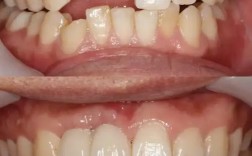

- 临床检查:通过牙周探诊测量牙周袋深度、附着丧失,结合X线片或CBCT评估骨缺损的类型、范围和程度。

- 常用“梯形切口”或“龈沟内切口”,翻开黏骨膜瓣,充分暴露骨缺损区。